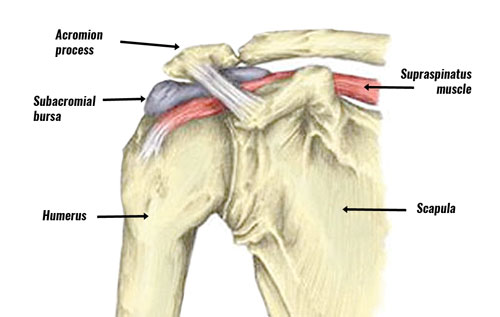

Fizioterapia dhe Pleksusi Brakial!

Çfarë është Pleksusi Brakial? Pleksusi brakial është një rrjet nervash që dalin nga qafa dhe kontrollojnë lëvizjen dhe ndjeshmërinë e shpatullës, krahut dhe dorës. Dëmtimet e pleksusit brakial mund të ndodhin nga trauma, aksidente, lindje e vështirë ose pozicione të gabuara të zgjatura, duke shkaktuar: Roli i Fizioterapisë në Trajtim…